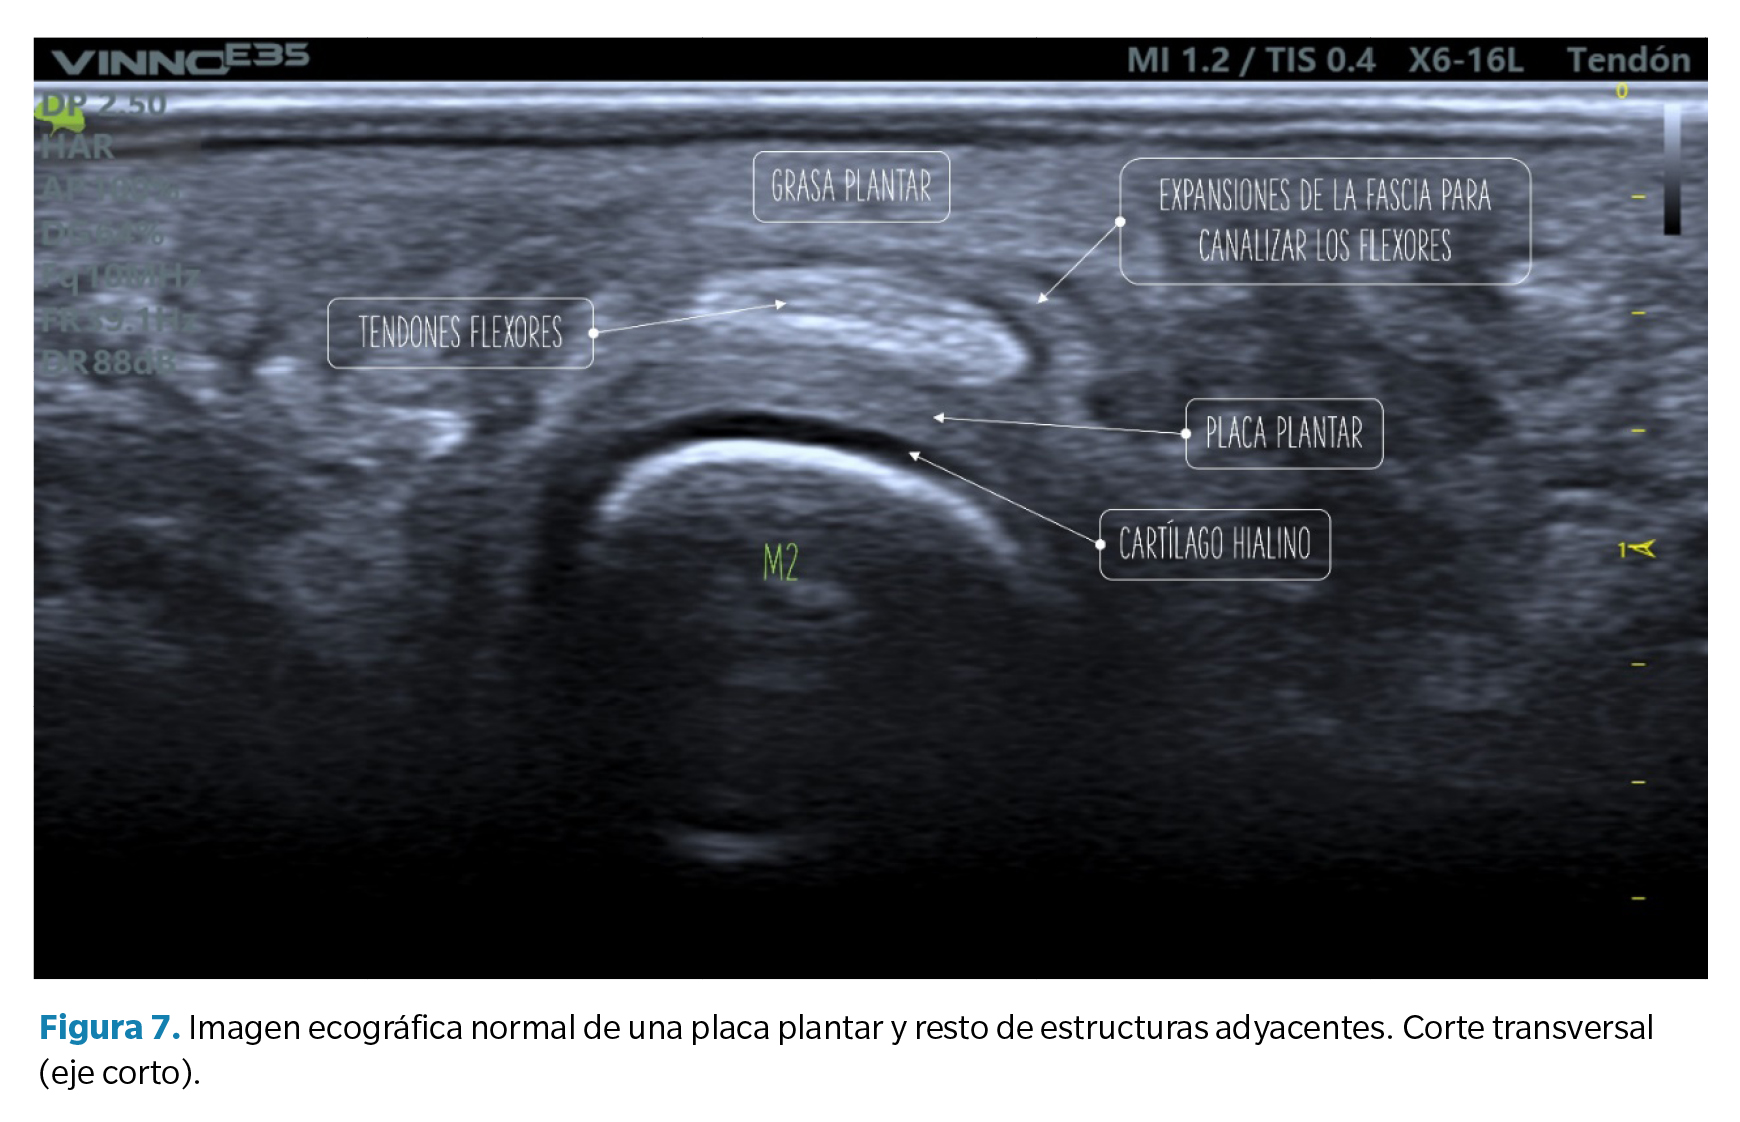

1. Defecto focal anecoico o hipoecoico. Se aprecian como una hendidura discreta en la zona profunda del tejido (zona que articula con la cabeza metatarsal) en su margen lateral. Cuando las fibras superficiales están intactas hablamos de un desgarro de espesor parcial, mientras que cuando dicho desgarro atraviesa todo el tejido hasta su región superficial hablamos de un desgarro de espesor total39 (Figura 8).